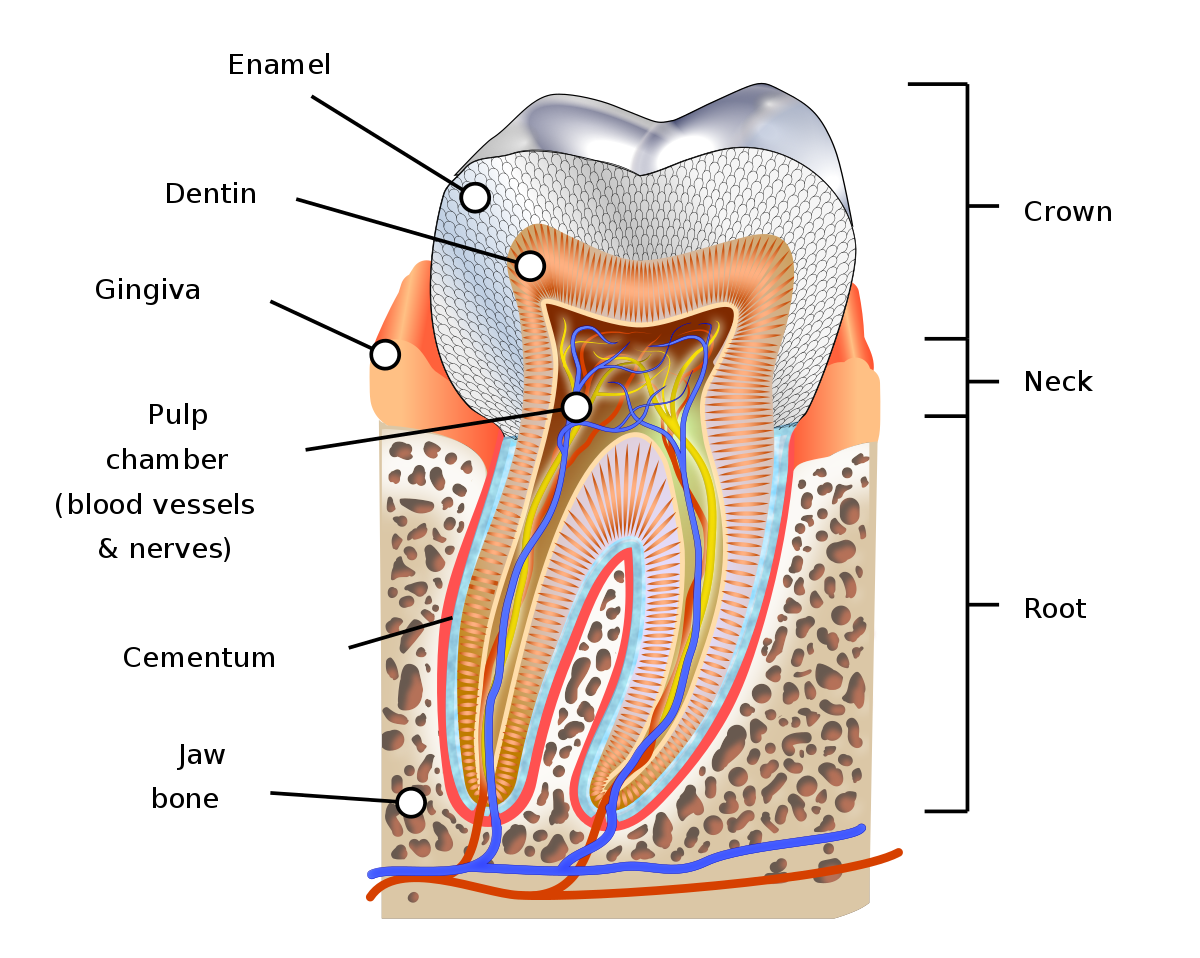

Anatomi gigi

Gigi - Wikipedia bahasa Indonesia, ensiklopedia bebas

Mengenal Anatomi Gigi, Jenis-Jenis Gigi, dan Fungsi Tiap Bagiannya

Mengenal Anatomi Gigi, Jenis-Jenis Gigi, dan Fungsi Tiap Bagiannya

Struktur Anatomi Gigi - Pentingnya Menjaga Kesehatan Gigi Kita

Struktur Anatomi Gigi - Pentingnya Menjaga Kesehatan Gigi Kita

Gigi : Pengertian, Bagian, Jenis, Morfologi dan Strukturnya

Gigi : Pengertian, Bagian, Jenis, Morfologi dan Strukturnya

BAB I Anatomi Gigi

BAB I Anatomi Gigi

Struktur Dan Anatomi Gigi - [PDF Document]

Struktur Dan Anatomi Gigi - [PDF Document]

Pengertian Gigi - Bagian, Lapisan, Susunan, Macam, Contoh

Pengertian Gigi - Bagian, Lapisan, Susunan, Macam, Contoh

Struktur dan Fungsi Gigi pada Manusia

Struktur dan Fungsi Gigi pada Manusia

Gigi: Anatomi dan Jenisnya Halaman all - Kompas.com

Gigi: Anatomi dan Jenisnya Halaman all - Kompas.com